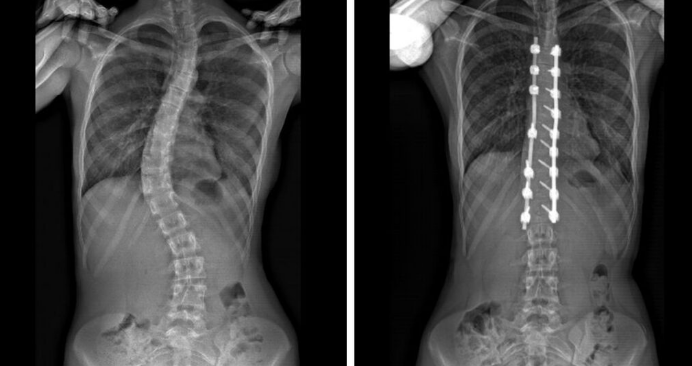

Scoliosis, not to be confused with silicosis, is a condition that causes a sideways curvature of the spine and affects around 3 percent of the population in the United States. While spines are naturally curvy, when viewed from the back, a typical spine will appear straight. Those with scoliosis, however, will usually develop a S-shaped or C-shaped curvature. This condition, although the exact cause is unknown, usually develops in adolescents, being especially prominent in females. It can be attributed to a variety of factors including genetics, family history, growth imbalances, being a byproduct of another disease, genetic disorder, or trauma.

Symptoms include uneven shoulders or hips, more prominent shoulder blades, back pain, and in some cases, breathing problems. When healthcare professionals diagnose this condition, a normal procedure would include an evaluation of family history, a physical exam, and an x-ray. Through this, doctors can best judge its severity and what a suitable treatment would be. If the condition is mild, the patient may only be subjected to regular checkups and observation in case of further progression, which is common especially among pre-pubescents. If the condition is moderate–around 20 to 40 degrees– the patient will be advised to wear a back brace, which prevents the spine from further progressing. In some cases, the back brace may even reverse the curvature of the spine. In addition to bracing, physical therapy may also be incorporated. In severe cases, spinal surgery will be needed to prevent further complications. There are two types of surgery: spinal fusion, which helps straighten the curve by joining vertebrae together, or the insertion of an expandable rod, where a surgeon may lengthen an inserted rod as the patient grows, making it optimal for those younger.